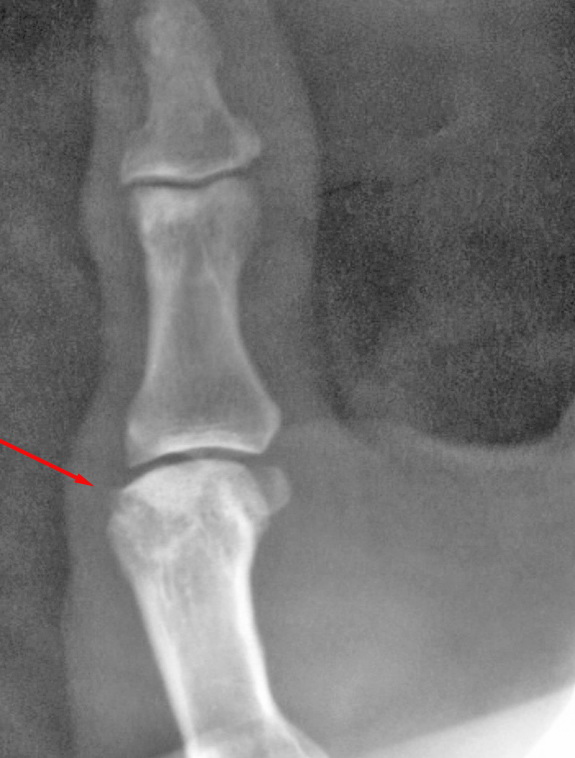

男,60,拇指掌指及指间关节疼痛15天。第一掌骨头低密度及箭头所指骨样突起正常吗

第一掌骨头局部低密度,考虑退变吧

手部经常可见囊状低密度区,可能为纤维性改变,无临床意义

箭头所指考虑纤维性骨皮质缺损。没有临床意义